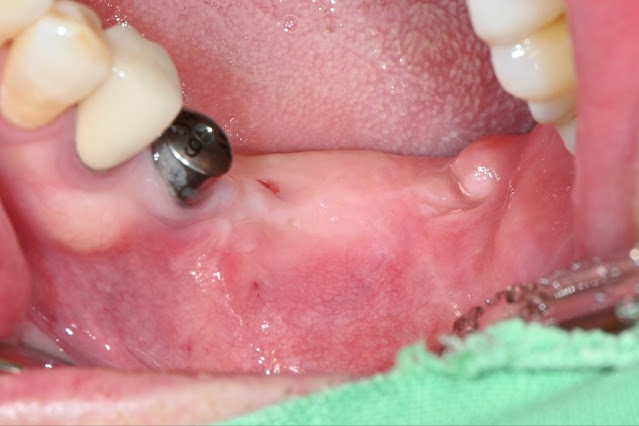

Replacing one fixture with OSSTEOBIONICS STR fixture

I used the STR fixture.  It is 4.5 mm in diameter and 10 mm long.  This is a case of removing a fixture that had been used for a long time, waiting, and then placing it with a delay.